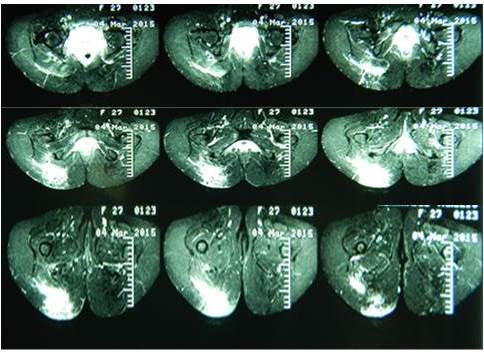

La RMN es el estudio de elección para los tumores en la región glútea permitiendo evaluar bien la tumoración y su relación los las estructuras musculares, óseas y nerviosas presentes en ese espacio (Figura 6) (2,6).